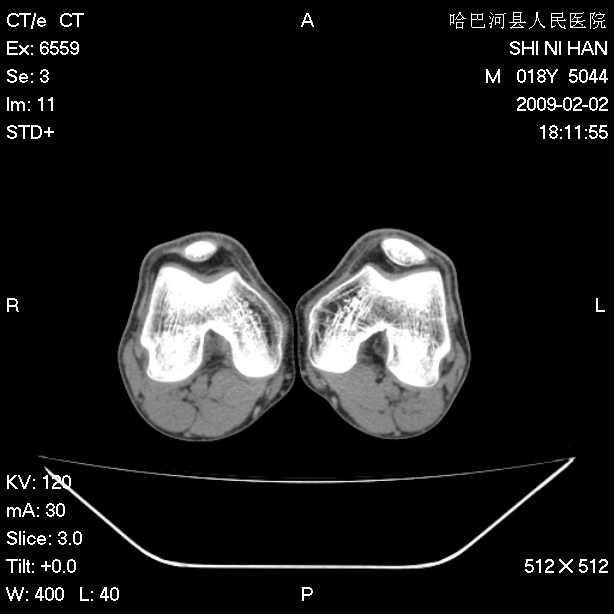

标题: CT17889:外伤后右膝关节反复疼痛3年余 [打印本页]

标题: CT17889:外伤后右膝关节反复疼痛3年余

ct未见明显异常。关节腔未见明显积液,半月板未见明显撕裂。但最好还是mri看看韧带及半月板情况。